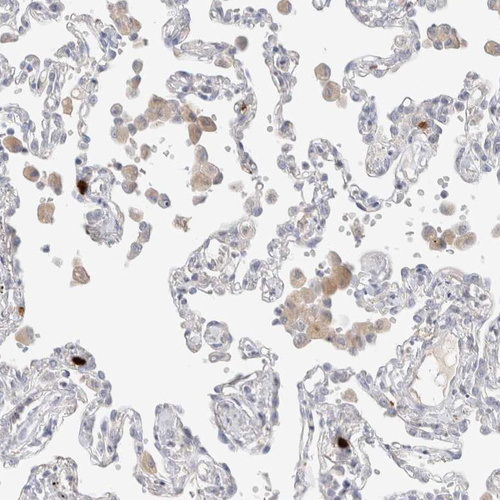

Immunohistochemical staining of human bone marrow shows moderate cytoplasmic positivity in megakaryocytes.